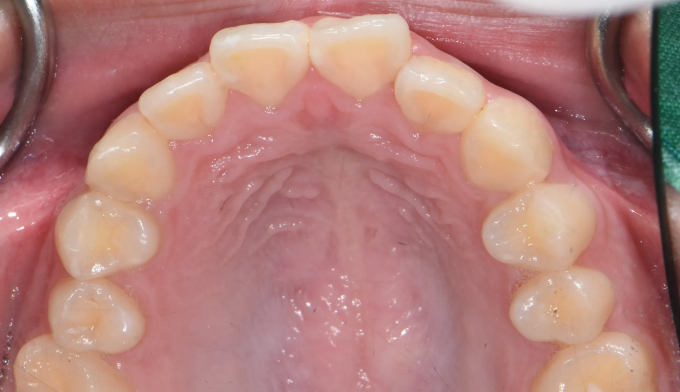

Before